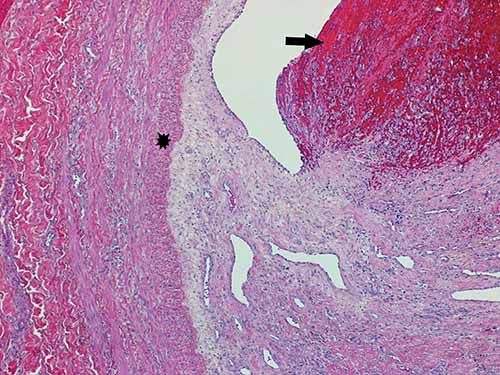

Histologic sections of thromboemboli are advised. While there may be thrombi of varying ages within the same vein, determining the oldest age is typically of most importance in medicolegal cases. Examination of the thrombo-endothelial junction can yield particularly helpful information such as whether there is hemosiderin, endothelial proliferation, collagen deposition, or neovascularization. While a variety of systems have been proposed to help date thromboemboli, caution is advised. There can be individual variation which precludes exact age determination. Providing a general categorization of thromboemboli as acute, organizing, or remote and opining as to whether this categorization seems consistent with a given clinical history may, however, be possible. Immunohistochemical stains for platelets (e.g., CD61), macrophages (e.g., CD68), leukocytes (e.g., CD45), neutrophils (e.g., CD15), and fibrinogen may be helpful in aging thromboemboli. Acute thromboemboli can be roughly characterized as having Lines of Zahn with no visible reaction between the endothelium and thrombus, and agglomeration of erythrocytes; the age is typically < 7 days. Organizing thromboemboli demonstrate fibroblast proliferation, endothelial budding, fibrinous transformation, and hemosiderin-laden macrophages; the age is roughly considered to be between 2–8 weeks (Figures 24-4 and 24-5). Remote thromboemboli are largely hyalinized with recanalization and are generally considered to be older than 2 months.

Figure 24-18 Lemierre’s Syndrome: septic thrombus within right internal jugular vein (H&E, 20×). Inset: Alternating bacterial colonies, fibrin lines, and fresh blood within thrombus (H&E, 400×).